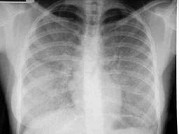

- 单项选择题女,18岁, 呼吸困难,消瘦, 糖原PAS染色阳性,结合图像, 最可能的诊断是 ( )

E、肺泡蛋白沉积症